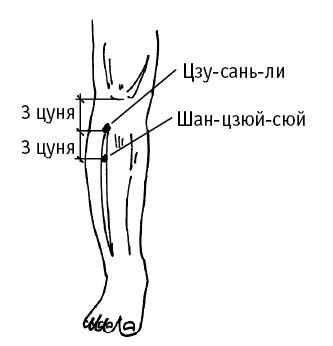

Цзу-сань-ли («нога» и «селения, расположенные на проезжих путях») расположена на 3 цуня ниже колена, на 1 цунь кнаружи от середины голени.

Используется для нормализации артериального давления.

Дополнительный эффект от воздействия на точку: лечение желудочно-кишечного тракта (боли в эпигастральной области, рвота, вздутие и урчание в животе, понос, постоянное чувство голода, холод в желудке, запоры); лечение гинекологических заболеваний (нарушение менструального цикла, дисфункциональные кровотечения, бели, бесплодие, выпадение матки, маститы); избавление от депрессии, бессонницы, сердцебиения; избавление от нарушений водного обмена (отеки, одышка); лечение кожных заболеваний (экзема, крапивница); нормализация артериального давления при гипертонии; повышение остроты зрения; лечение болей в суставах ноги, избавление от мышечной слабости.

Цзу-сань-ли («нога» и «селения, расположенные на проезжих путях») расположена на 3 цуня ниже колена, на 1 цунь кнаружи от середины голени.

Точку используют при боли в эпигастральной области, рвоте, вздутии живота, урчании в животе, поносе, постоянном чувстве голода, холоде в желудке, при запорах.

Дополнительный эффект от воздействия на точку: лечение гинекологических заболеваний (нарушение менструального цикла, дисфункциональные кровотечения, бели, бесплодие, выпадение матки, маститы); избавление от депрессии, бессонницы, сердцебиения; избавление от нарушений водного обмена (отеки, одышка); лечение кожных заболеваний (экзема, крапивница); нормализация артериального давления при гипертонии; повышение остроты зрения; лечение болей в суставах ноги, избавление от мышечной слабости.

Шан-цзюй-сюй («огромная верхняя пустота») расположена на 6 цуней ниже верхнего края латерального мыщелка большой берцовой кости (поднимите ногу, у латерального края большеберцовой кости образуется большая длинная впадина). Или еще проще: на 3 цуня ниже точки Цзу-сань-ли.

Используйте точку при ощущении стремительного поднятия газов от живота к грудной клетке, при боли в эпигастральной области, рвоте, вздутии живота, урчании в животе, при поносах или несварении, при запорах.

Воздействие на шан-цзюй-сюй полезно также: при мышечной слабости, боли в суставах нижних конечностей; при болезнях водного обмена (отеки лица и конечностей); при затрудненном мочеиспускании, боли вокруг пупка.

Цзу-сань-ли («нога» и «селения, расположенные на проезжих путях») расположена на 3 цуня ниже колена, на 1 цунь кнаружи от середины голени.

Используется для нормализации артериального давления.

Дополнительный эффект от воздействия на точку: лечение желудочно-кишечного тракта (боли в эпигастральной области, рвота, вздутие и урчание в животе, понос, постоянное чувство голода, холод в желудке, запоры); лечение гинекологических заболеваний (нарушение менструального цикла, дисфункциональные кровотечения, бели, бесплодие, выпадение матки, маститы); избавление от депрессии, бессонницы, сердцебиения; избавление от нарушений водного обмена (отеки, одышка); лечение кожных заболеваний (экзема, крапивница); нормализация артериального давления при гипертонии; повышение остроты зрения; лечение болей в суставах ноги, избавление от мышечной слабости.

Цзу-сань-ли («нога» и «селения, расположенные на проезжих путях») расположена на 3 цуня ниже колена, на 1 цунь кнаружи от середины голени.

Точку используют при боли в эпигастральной области, рвоте, вздутии живота, урчании в животе, поносе, постоянном чувстве голода, холоде в желудке, при запорах.

Дополнительный эффект от воздействия на точку: лечение гинекологических заболеваний (нарушение менструального цикла, дисфункциональные кровотечения, бели, бесплодие, выпадение матки, маститы); избавление от депрессии, бессонницы, сердцебиения; избавление от нарушений водного обмена (отеки, одышка); лечение кожных заболеваний (экзема, крапивница); нормализация артериального давления при гипертонии; повышение остроты зрения; лечение болей в суставах ноги, избавление от мышечной слабости.

Шан-цзюй-сюй («огромная верхняя пустота») расположена на 6 цуней ниже верхнего края латерального мыщелка большой берцовой кости (поднимите ногу, у латерального края большеберцовой кости образуется большая длинная впадина). Или еще проще: на 3 цуня ниже точки Цзу-сань-ли.

Используйте точку при ощущении стремительного поднятия газов от живота к грудной клетке, при боли в эпигастральной области, рвоте, вздутии живота, урчании в животе, при поносах или несварении, при запорах.

Воздействие на шан-цзюй-сюй полезно также: при мышечной слабости, боли в суставах нижних конечностей; при болезнях водного обмена (отеки лица и конечностей); при затрудненном мочеиспускании, боли вокруг пупка.